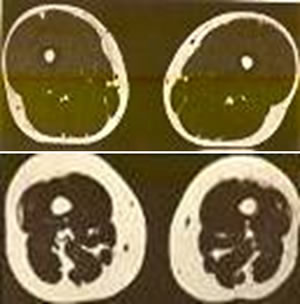

Con la edad y falta de actividad física el tejido muscular se debilita y es reemplazado por grasa. (A la izquierda: corte transversal del muslo de una mujer joven; a la derecha: de una mujer mayor, de la misma estatura y peso. La grasa es lo blanco, el músculo es lo oscuro.) Factores principales de la degradación muscular: falta de ejercicio dietas de hambre falta de proteína en los alimentos.